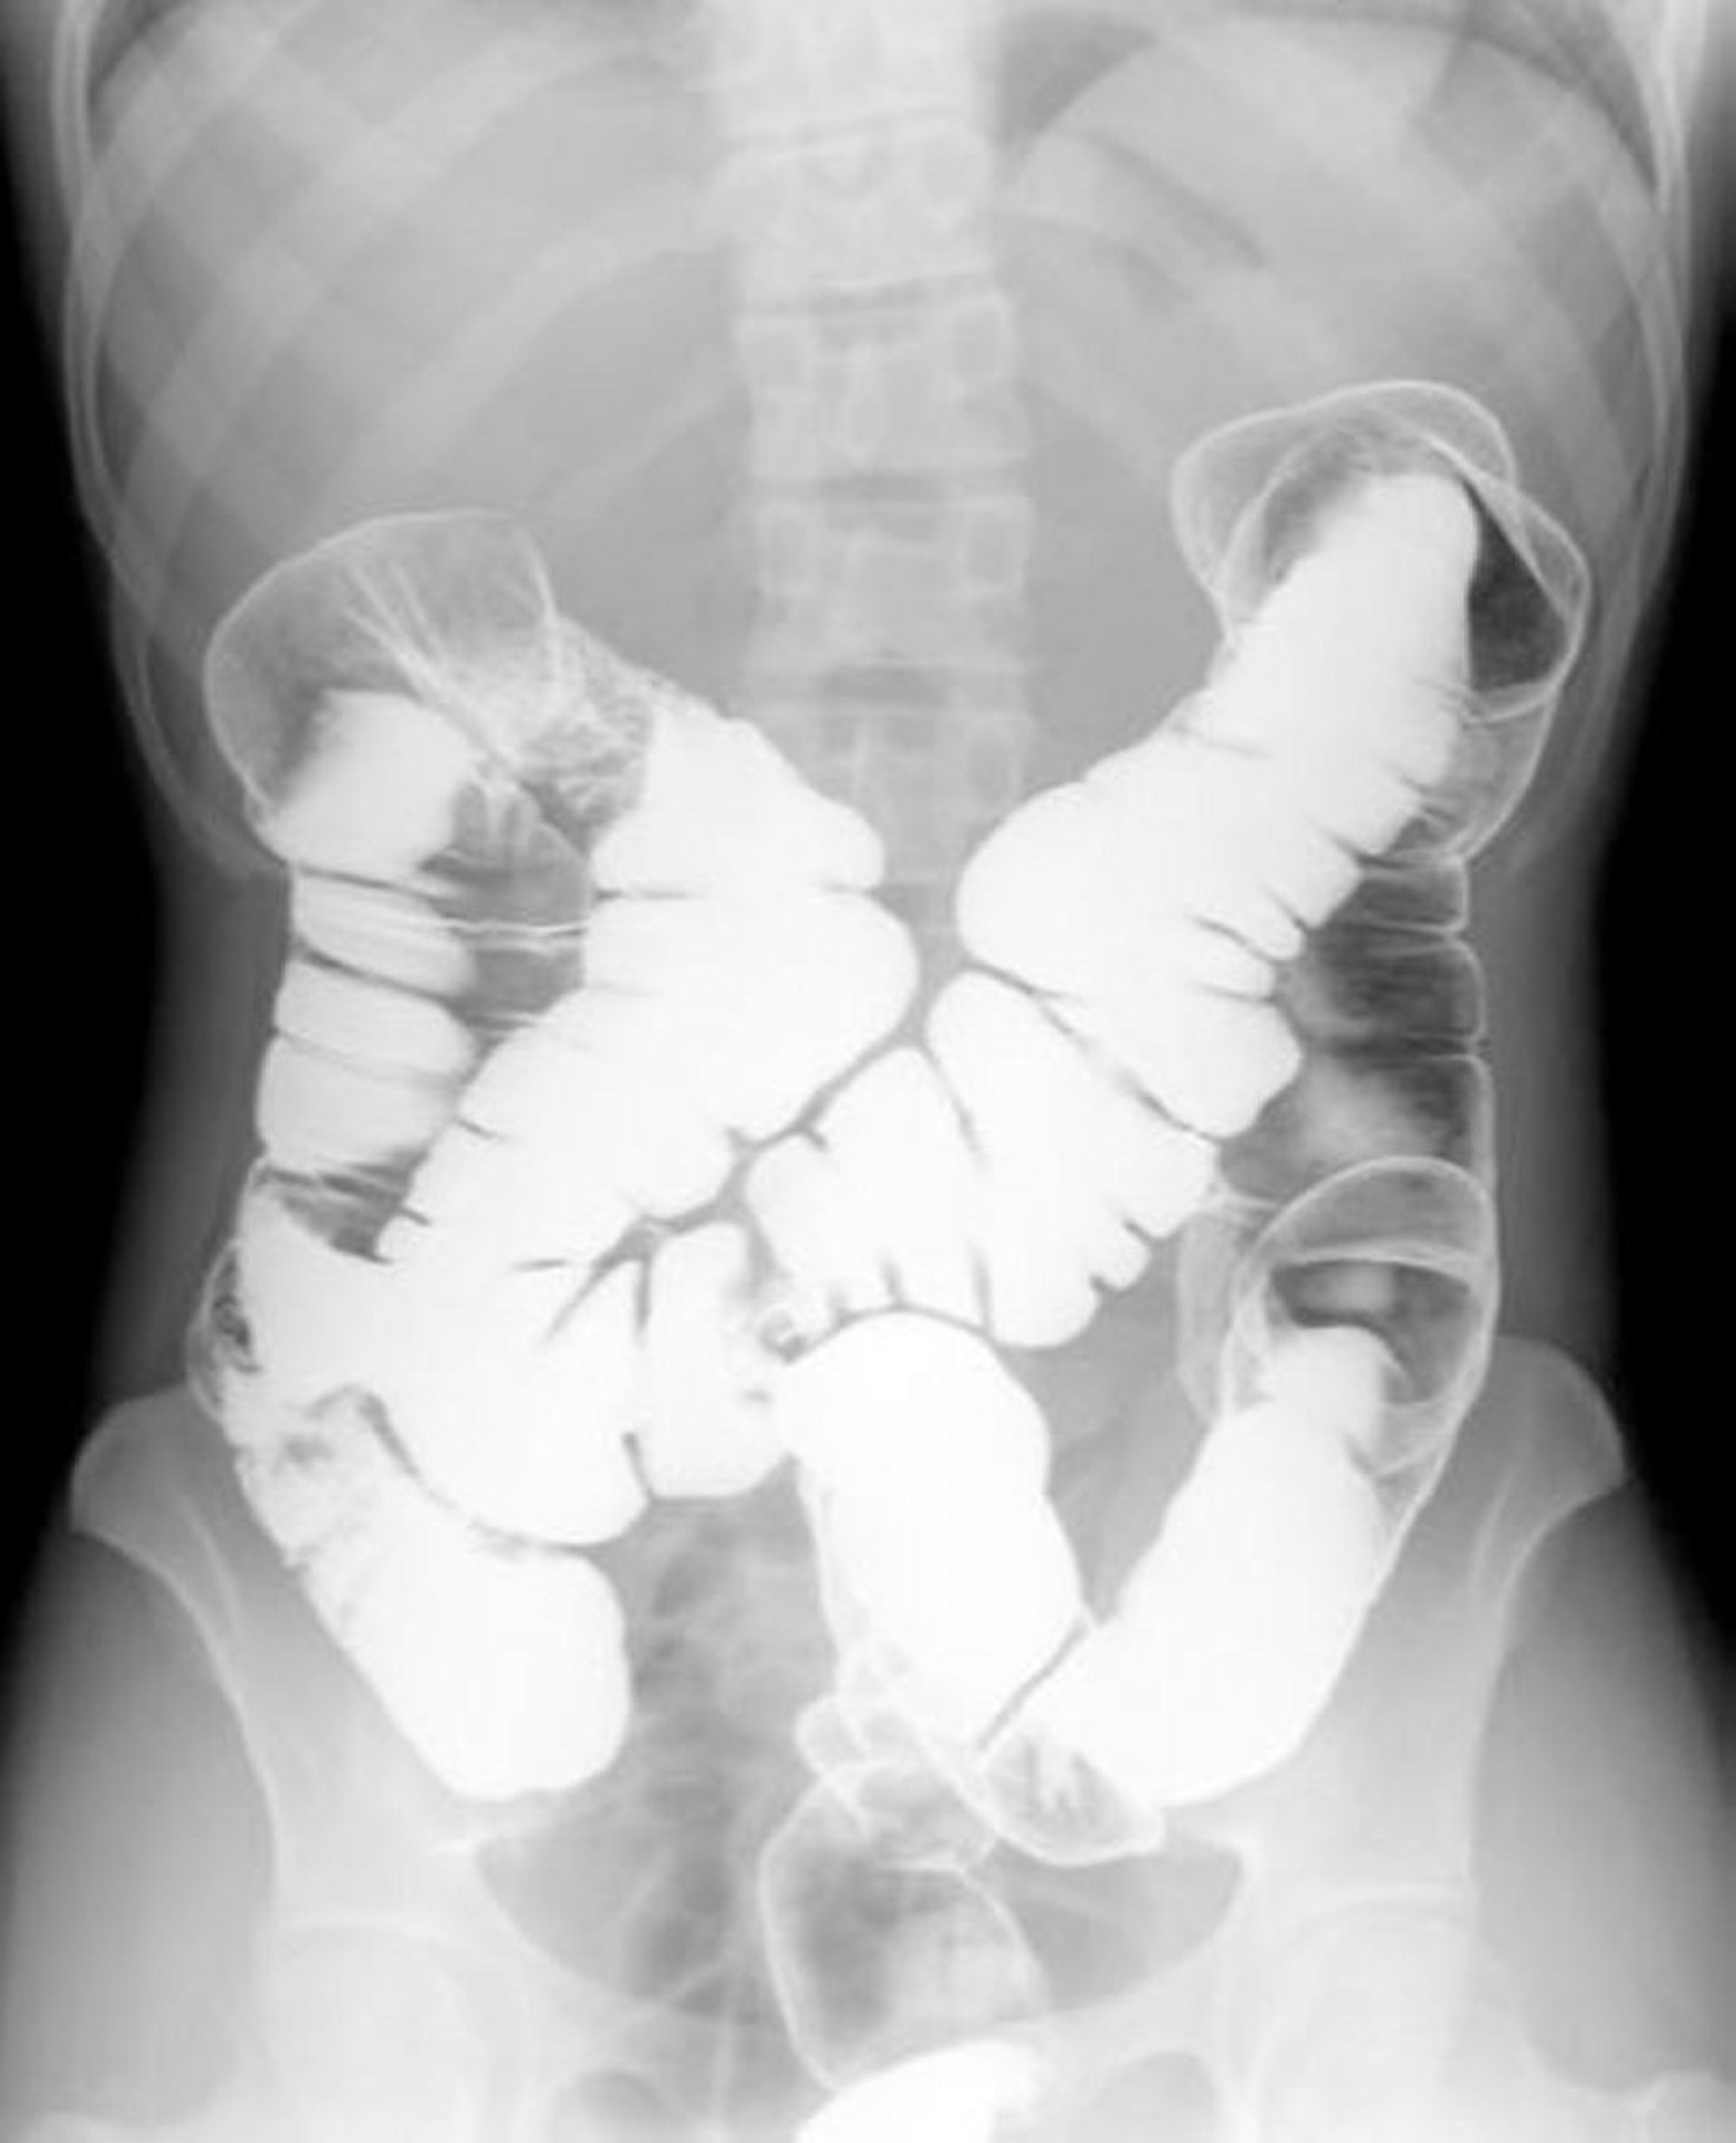

Clisma opaco con doppio contrasto che mostra anatomia normale

Questa immagine mostra il modello di aria e bario all'interno di un colon normale.